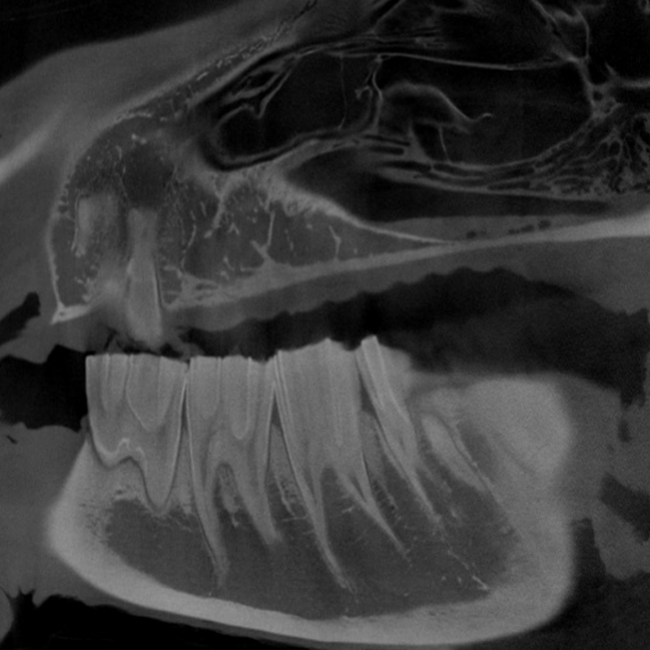

Oris Dental CT

High Definition Volumetric Imaging (HDVI) technology